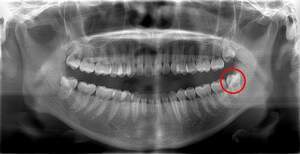

右下の親知らずが疼く症例

- 抜歯前写真(レントゲン)

- 抜去歯の写真(CT画像)

| 年齢 | 30代・女性 |

|---|---|

| 主訴 | 右下親知らずが疼く |

| 親知らずの生え方 | 横向きに生えている |

| 抜歯時間 | 40分 |

| 費用 | 約8,000円(保険診療、CT代含む) |

| 抜歯内容 | 右下の親知らずは横向きに生えて埋まっているため、麻酔をし親知らずの奥に切開を入れて歯ぐきを開き、歯を囲んでいる骨を削り歯の頭部分を割って出してから、残った根の部分を取り出して抜歯は終了しました。 歯ぐきを切った部分は糸で縫っています。このケースでは根の先端が神経に近く麻痺のリスクがありましたが事前にCTを撮影し、神経との位置関係を確認していたため、麻痺が残ることはありませんでした。 約1週間後に糸取りを行い、その際も多少の痛みや腫れはありましたが後日その痛みも無くなりました。 |